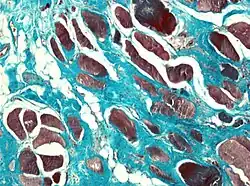

Muscle biopsies are also a useful tool to diagnose camptocormia. Muscle biopsies found to have variable muscle fiber sizes and even endomysial fibrosis may be markers of bent spine syndrome. In addition, disorganized internal architecture and little necrosis or regeneration is a marker of camptocormia.

Patients with camptocormia present with reduced strength and stooped posture when standing due to weakened paraspinous muscles (muscles parallel to the spine). Clinically, limb muscles show fatigue with repetitive movements.[5] Paraspinous muscles undergo fat infiltration. Electromyography may be used as well in diagnosis. On average, the paraspinous muscles of affected individuals were found to be 75% myopathic, while limb muscles were 50% percent myopathic.[5] Creatine kinase activity levels in skeletal muscle are a diagnostic indicator that can be identifiable through blood tests.